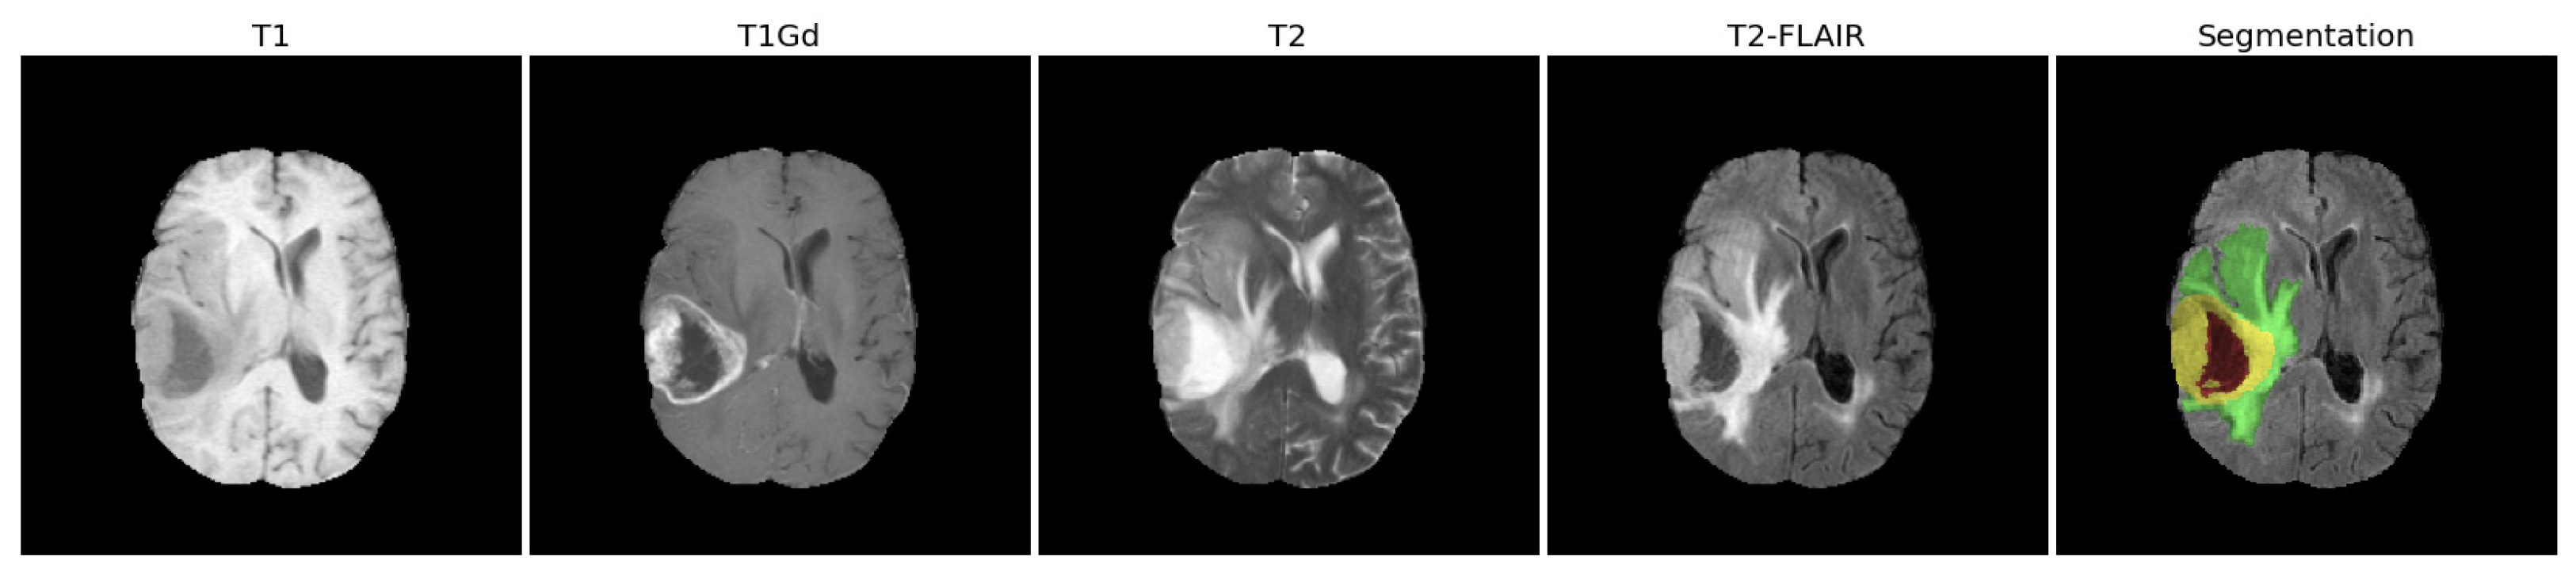

- Feature extraction: for each patient, we extracted the radiomic features from the whole tumor (WT) volume in the four MRI scans (T1, T1Gd, T2, T2-FLAIR).